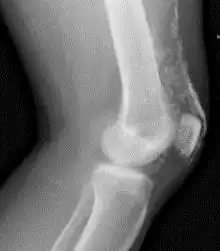

Röntgenfoto van een knie bij dermatomyositis. | ||||